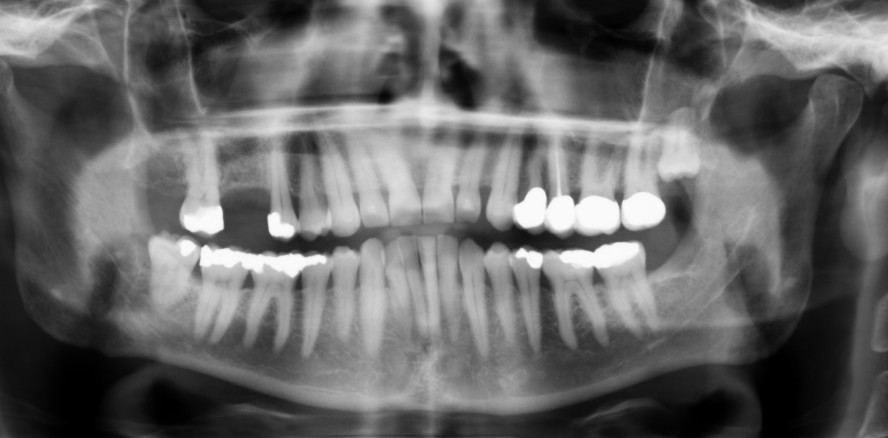

Foto: Dr. Kaiser

Patientenfall